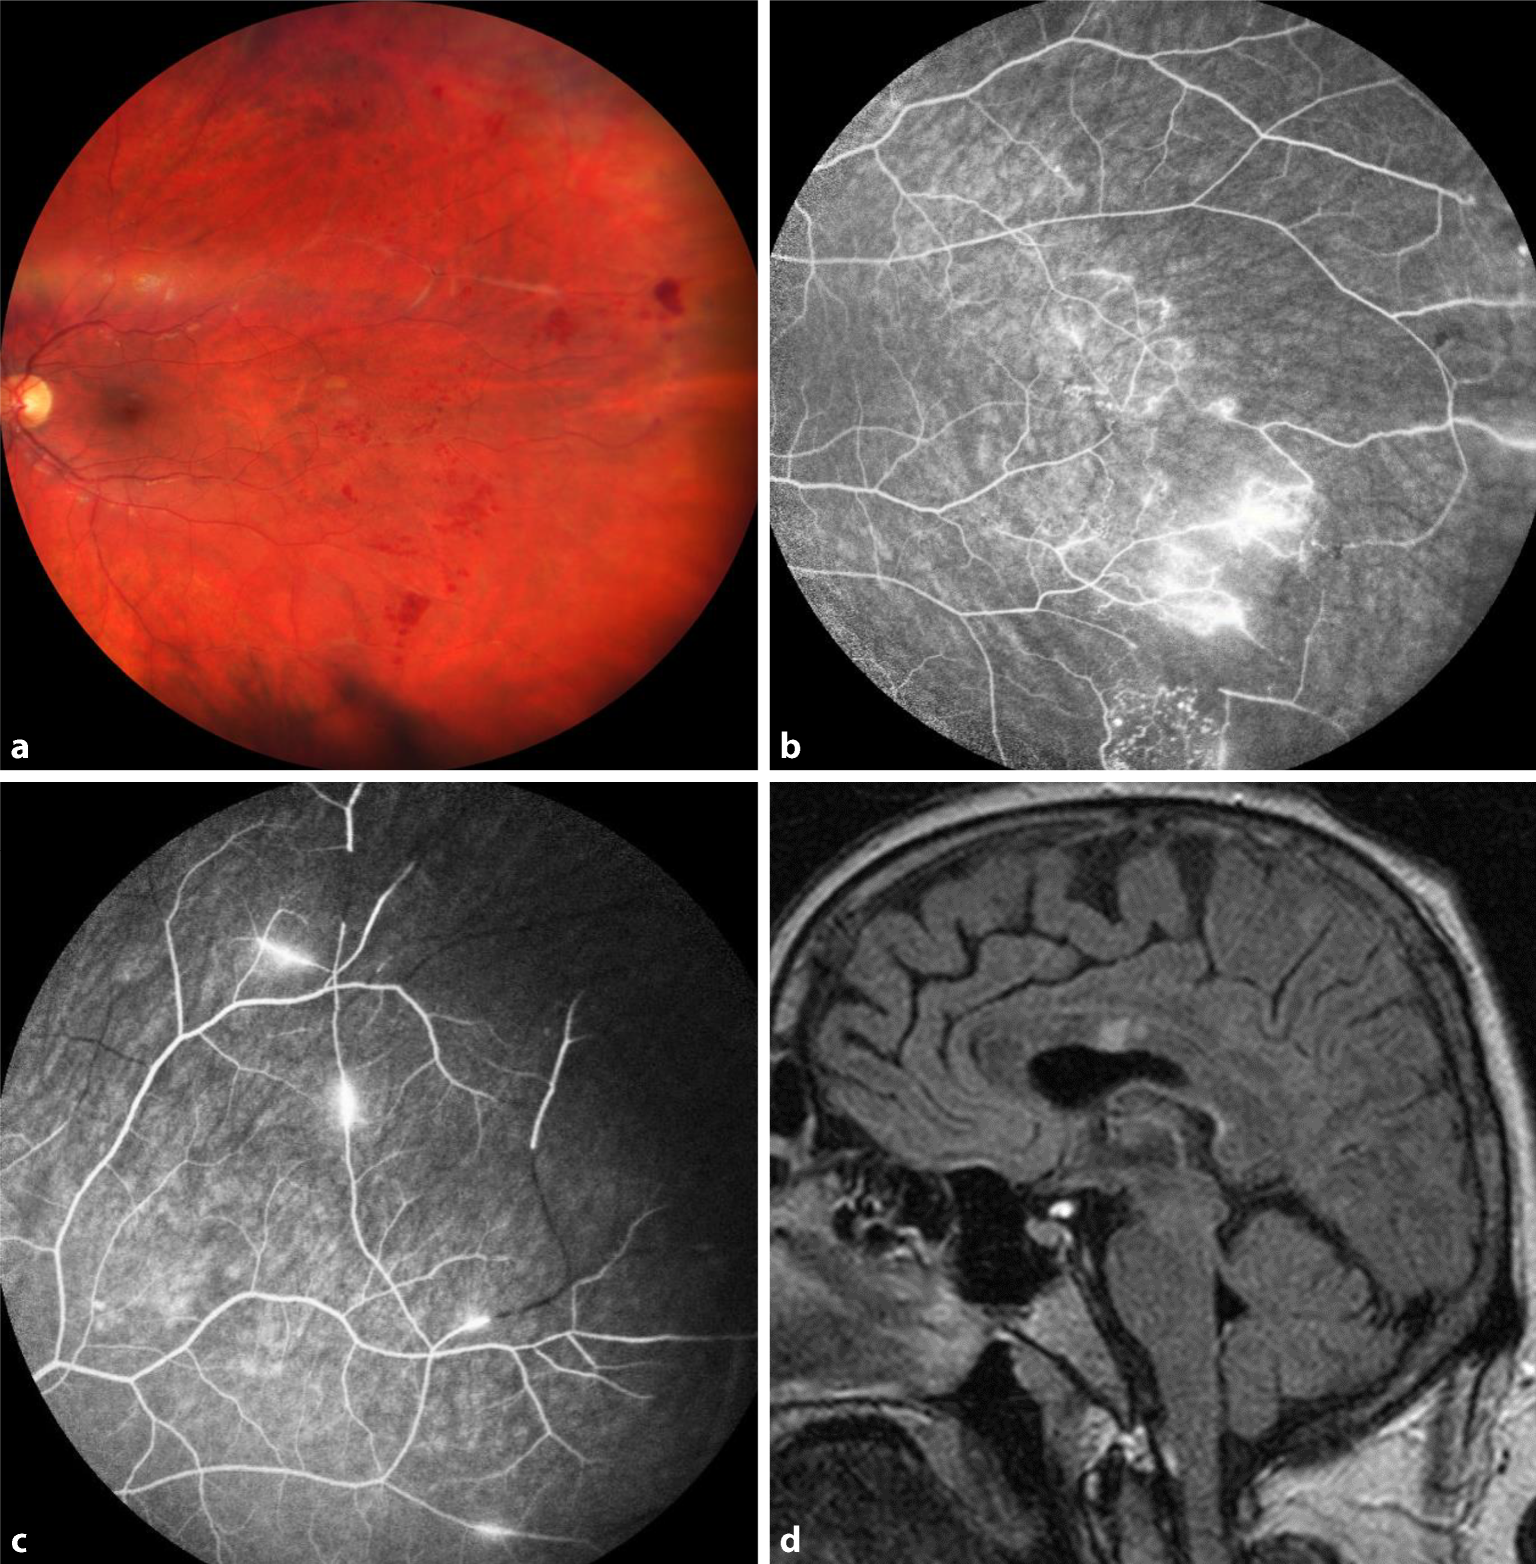

Ophthalmologische Befunde umfassen fokale, segmentale, arterioläre Verengungen, Cotton-wool-Herde, ein Papillenödem, perivaskuläre Einscheidungen sowie periphere Gefäßverschlüsse (Abb. 7). Die FAG zeigt zudem segmentale arterielle Hyperfluoreszenzen (Abb. 7) und ist daher für die Diagnose obligatorisch [20].

Abb. 7

Veränderungen bei Susac-Syndrom. a Fundusbild mit Gefäßeinscheidungen und peripheren retinalen Hämorrhagien. bc Fluoreszenzangiographie mit peripheren Gefäßokklusionen und segmentaler Vaskulitis. d T2-MRT (Magnetresonanztomographie) mit hyperintenser Läsion im Bereich des Corpus callosum

Susac-Syndrom

Das Susac-Syndrom ist eine seltene autoimmune entzündliche Enzephalopathie, die eine Mikroangiopathie verursacht. Sie ist durch eine klassische Trias aus neurosensiblem Hörverlust, Enzephalopathie und okklusiver retinal-arterieller Vaskulitis gekennzeichnet. Die Erkrankung betrifft ebenfalls insbesondere junge Frauen [17]. Bei Erstmanifestation weisen nur 15 % die vollständige klinische Triade auf. Die Pathogenese ist unklar. Antiendothelzellantikörper werden bei bis zu 30 % der Patienten gefunden. Diese sind jedoch nicht spezifisch und können auch bei anderen entzündlichen Erkrankungen gefunden werden. Symptomatisch leiden 80 % der Patienten zunächst an Kopfschmerzen im Rahmen der Enzephalopathie [18]. Fortschreitend kann es zu einem zunehmenden Gedächtnisverlust, Konzentrationsstörung, Desorientierung und Verhaltensänderungen kommen. Die zerebrale Beteiligung wird durch typische MRT-Befunde in T2- oder FLAIR-gewichteten Sequenzen als hyperintensive, multifokale, runde kleine Läsionen im Corpus callosum nachgewiesen. Die Beteiligung des vestibulocochleären Systems zeigt sich zunächst als niederfrequenter sensorineuraler Hörverlust im Audiogramm. Peripherer Schwindel, Nystagmus und Tinnitus treten oft assoziiert auf [19].